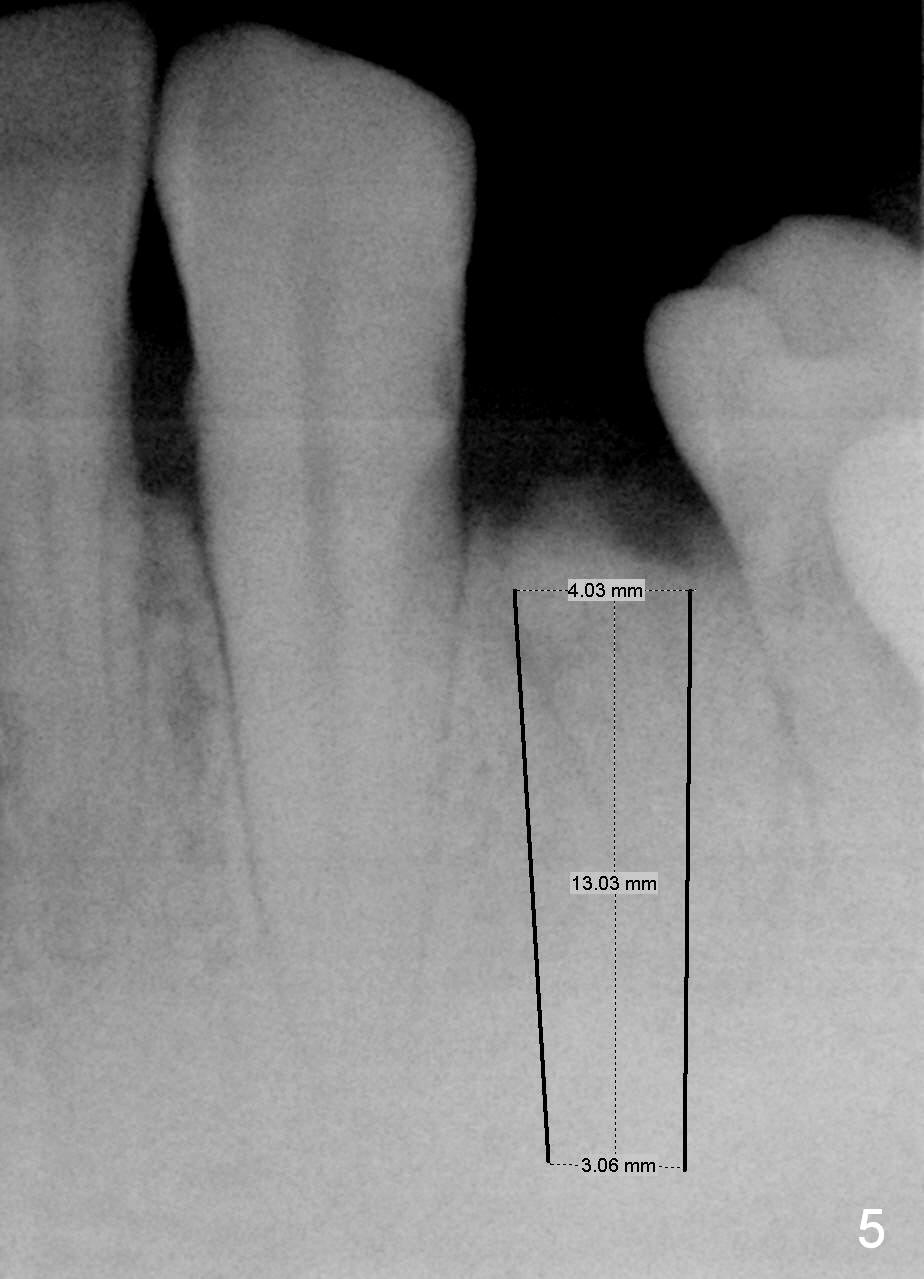

A 48-year-old man requests restoring the fractured tooth #21 (Fig.1). The socket seems to be oblique (Fig.2, no Antibiotic). Also considering the thin buccal plate, the initial osteotomy should be established in the mesiolingual slope (Fig.3). Change the trajectory once the entry is made (Fig.4) and take PA for confirmation. A 4x13 mm implant is to be placed (Fig.5). Why should the implant placed lingually? In fact the implant is placed too lingually. What is the reason?